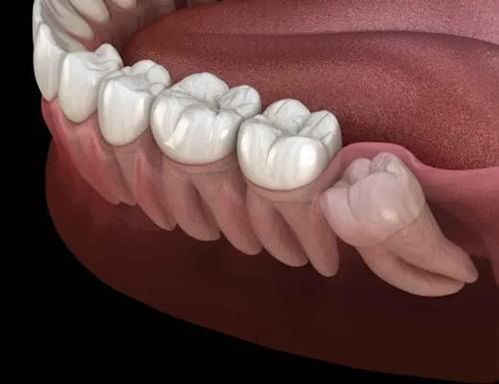

안녕하세요 목동안치과의 안상우 원장입니다.오늘은 사랑니에 대한 이야기를 한번해보고자 합니다.사랑니에 대해서는 한번쯤은 들어보신적이 있으실꺼에요.사랑니는 치아의 제일 뒤에 있는 치아로 제3대구치라고도 합니다. 막니라고도 해요.맨 뒤에 있기 때문에 인지를 못하는 경우도 있고 맨 뒤에 있기 때문에 관리하기가 쉽지 않습니다. 또한 잇몸 밖으로 나오지 않는경우도 있습니다.사랑니는 우리몸의 진화과정과 관련이 있습니다.먼 옛날 우리의 선조들의 음식들은 대부분 질긴경우가 많았어요.조리가 되지 않았거나 잘 다듬어지지 않은 음식 들이었겠죠질긴음식을 먹기 위해서는 턱이 커야 했고 치아가 많아야 했어요.그래서 사랑니가 정상적인 대구치처럼 사용되고 있었습니다.하지만 현대에 들어서 음식이 부드러워지고 섭취하기 쉬워지면서 현대인들은 원시의 선조들보다 턱의 크기가 작아지게 되었습니다.그러다보니 자연스럽게 맨 뒤에 있는 치아는 있을 자리가 없어지면서 비정상적인 형태로 나오기 시작했습니다.사랑니는 어떻게 보면 퇴화하는 기관중에 하나에요.이 사랑니는 어떤 경우에는 그냥 두거나 사용할수 있고 어떤경우에는 뽑아야 하는경우도 있습니다.사랑니는 치아 중 맨뒤에 나는 치아로 칫솔질로 관리하기 힘든 위치에 있습니다.정말 관심을 가지고 관리를 하지 않는 이상 이 부위에는 이물질이 자주 저류되게 되요.사랑니가 아예 잇몸안에 들어가 있다면 외부의 이물질이 들어가거나 하지 않기 때문에 문제를 발생시키지 않습니다.하지만 사랑니가 구강내로 부분적 또는 완전히 맹출했을 경우에는 사랑니 주변에 이물질이 남아 있을수 있습니다.우선 뽑아야 하는 사랑니중에 첫번째는 일단 충치가 생겨서 통증을 유발할 때입니다.이런경우에는 관리가 잘 안되는것이기 때문에 발치를 해주는것이 좋습니다.충치가 있어도 똑바로 나와 있으면 치료를 해서 사용할수도 있기는 합니다.하지만 치아가 뒤에 있어서 치료가 다른치아보다 상대적으로 어려워서 치료에 한계가 있을 수 있습니다.두번째 경우로는 사진과 같이 사랑니가 팔자좋게 옆으로 누워있다면 발치를 해야 하는 대표적인 사랑니중에 하나에요.사랑니가 기울어져 있게 되고 잇몸에 부분적으로 맹출되어 나와 있게 되면 사랑니와 앞에 있는 치아 사이에 음식물이 자주 들어 갈수 있습니다.이런식으로 잇몸에 염증을 일으킬수 있거나 앞에 치아에 충치를 발생시킬 가능성이 있는 사랑니라면 발치 해줘야 합니다.사랑니는 위아래 같이 존재하게 되는데 한쪽의 사랑니는 똑바로 나왔는데 다른 쪽 사랑니가 나오지 않았거나 발치되었다면 맹출되어 있는 사랑니가 정출될 수 있습니다.치아가 정출되게 되면 치열이 어긋나게 되어 해당부위에 음식물이 들어 갈수 있어요.또한 반대편 잇몸을 자극하게 되어 잇몸에 상처가 나고 통증이 있을수 있습니다.이런 경우에도 발치를 해야 하는경우입니다.일단 사랑니가 똑바로 나와 있고 위아래 치아가 정상적으로 교합을 하고 있다면 발치를 하지 않아도 됩니다.사랑니가 정상적으로 물리게 된다면 저작하는 기능이 증가하게 되어 다른 치아에 가해지는 힘을 분산하게 됩니다.또한 뽑지 않아도 되는 사랑니로는 완전하게 잇몸안에 들어가 있어서 앞의 치아나 잇몸에 이물질을 저류시키지 않는 경우 입니다.잇몸안에 완전히 들어가 있고 특별한 병소가 없다면 발치를 할필요가 없어요.어떻셨나요 자신의 사랑니를 뽑아야 하는지 아닌지는 사랑니가 난 형태와 위치를 확인해보세요.사랑니가 잘 기능을 하고 주변에 문제를 일으키지 않는지에 대해서 생각을 해본다면 발치를 해야 하는것인지 아닌지 구분을 할수 있습니다.치아는 하나라도 더 있는 것이 좋습니다.따라서 사랑니를 가지고 있으신분들도 사랑니라고 너무 소홀해 해지 마시고 관심을 가지고 관리를 해주는것이 좋습니다.